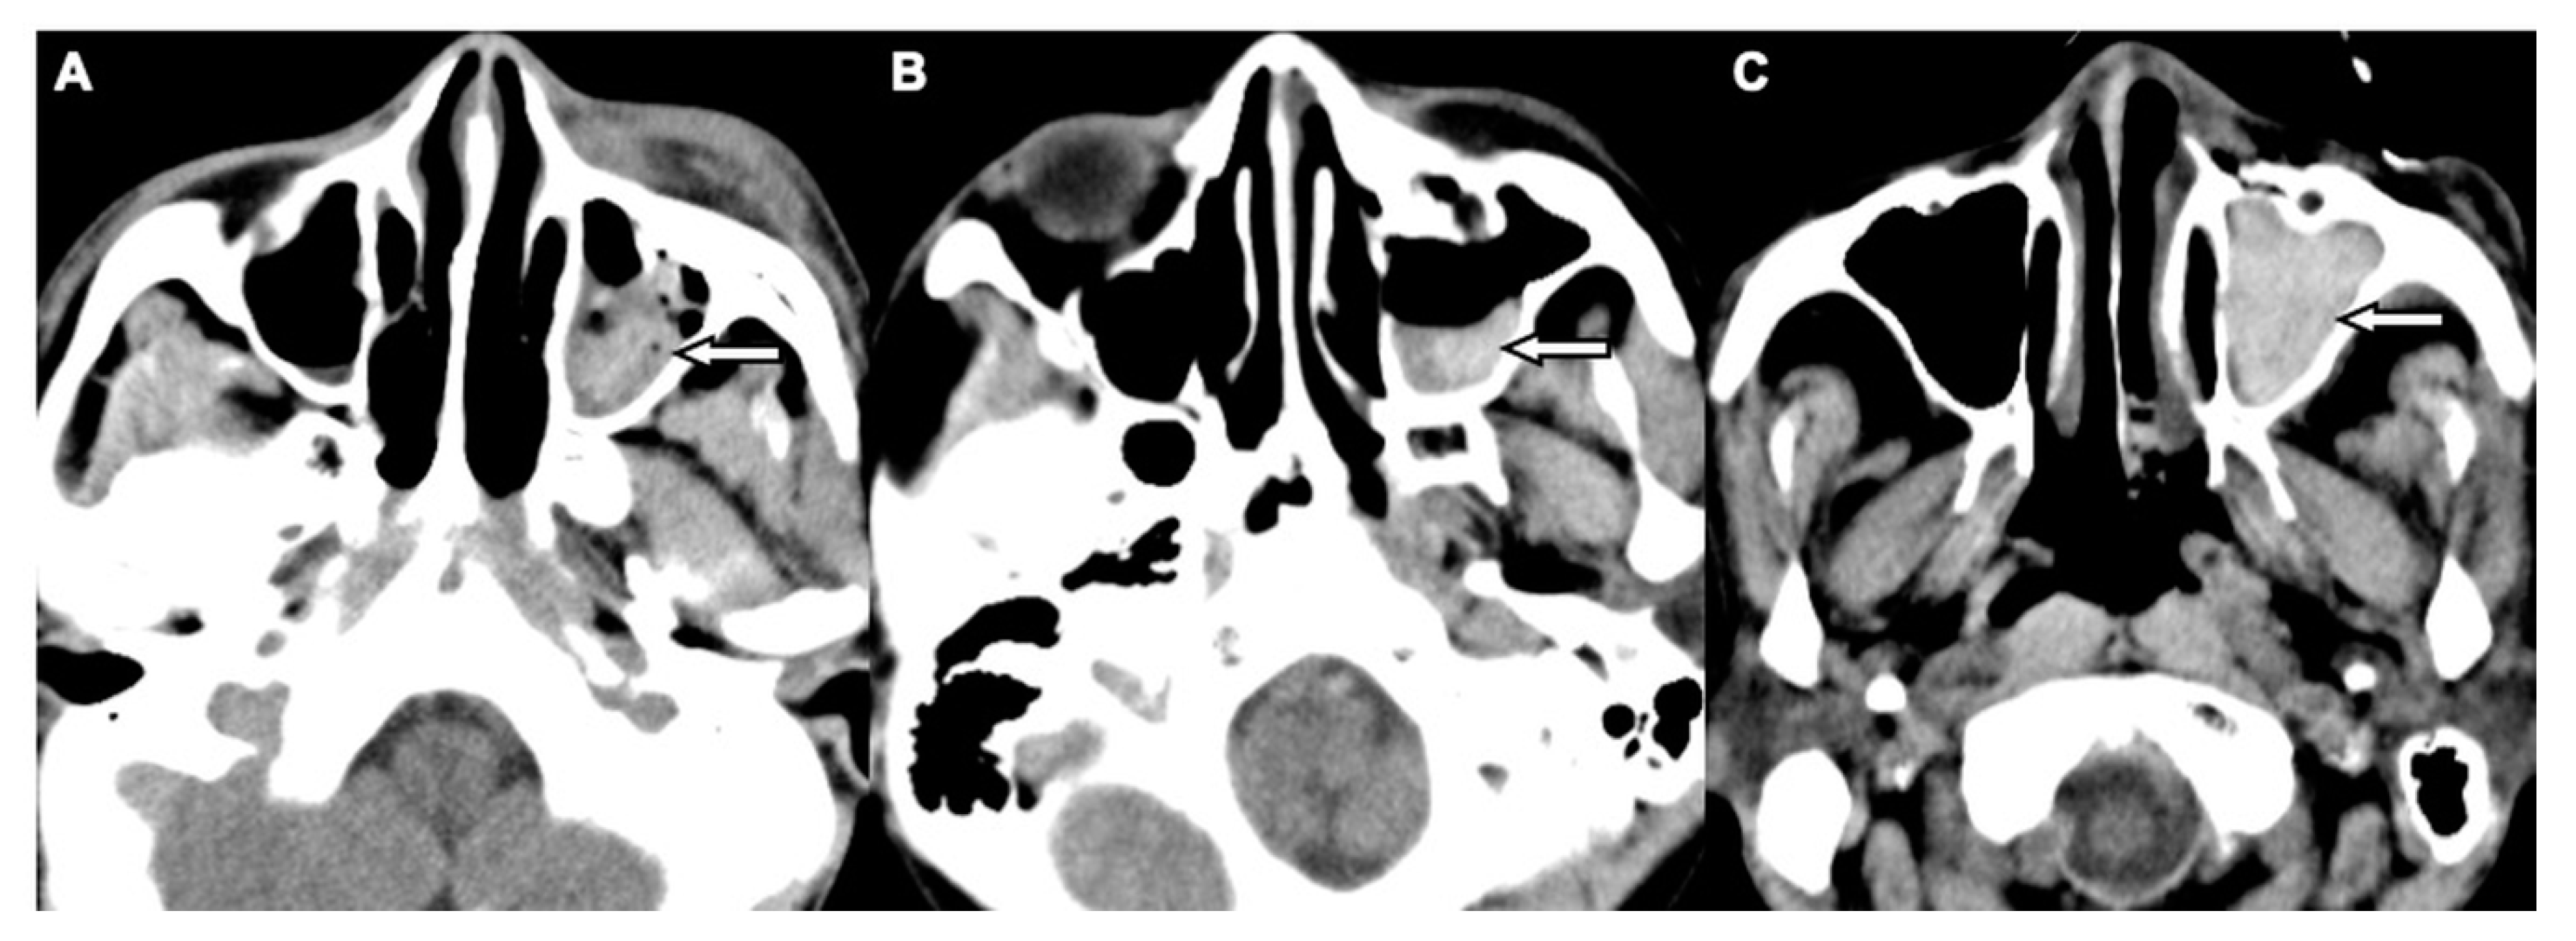

Figure 3. CT images showing three patterns of MHS related to OFFs associated with head trauma. (A) Type 1: high-attenuation opacity mixed with mottled gas in the left maxillary sinus (arrow) in a 52-year-old male with motorcycle crash-related head trauma. (B) Type 2: air–fluid level in the left maxillary sinus (arrow) in a 26-year-old female with motor vehicle collision-related head trauma. (C) Type 3: full opacification of the left maxillary sinus (arrow) in a 79-year-old male with fall accident-related head trauma.

Two board-licensed radiologists (L.D.J. and Y.Y.C.) who were blinded to the patients’ clinical information reviewed only the head CT images by means of consensus. The radiologists were permitted to manipulate the window and level of the images. The CT variables related to the cranium included intracranial hemorrhage (ICH; epidural hemorrhage, subdural hemorrhage, subarachnoid hemorrhage, and intracerebral hemorrhage), and skull fractures. The CT variables related to OFFs included orbital floor discontinuity (Figure 1), gas bubbles entrapped between the floor fragments (Figure 1), inferior extraconal emphysema (Figure 2), orbital fat herniation into the maxillary sinus (Figure 2), and ipsilateral maxillary hemosinus (MHS, Figure 3). MHS was defined as high-attenuation opacity at the dependent portion of the maxillary sinus measuring ≥ 45 Hounsfield units (HU) as the lower limit of attenuation for clotted blood [15]. Since MHS is a relevant indicator used to detect OFFs on CT scans [5,16], we further classified MHS into the following three CT subtypes: (1) Type 1, high-attenuation opacity mixed with mottled gas (Figure 3A); (2) Type 2, air–fluid level (Figure 3B); and (3) Type 3, full opacification of the sinus (Figure 3C).

The sensitivity, specificity, positive predictive value, and negative predictive value of MHS and its three subtypes were evaluated in detail (Figure 4). While MHS exhibited a very high negative predictive value (99.7%) for excluding OFFs, type 1 MHS had the highest positive predictive value (69.5%) for detecting OFFs compared to total MHS and the other two subtypes.

A subset imaging analysis for head trauma patients with MHS was conducted to investigate the correlation between subtypes of MHS and OFFs. Patients with non-orbital floor fractures which may result in MHS (sole maxillary bone or medial orbital wall, or both) were excluded from the non-OFF group. The comparisons of head CT variables between the OFF (n = 188) and non-OFF (n = 102) groups are shown in Table 3. The OFF group more commonly exhibited type 1 MHS, while types 2 and 3 MHS were more frequently observed in the non-OFF group. In the multivariate logistic regression analyses, after adjusting for other CT variables, only type 1 MHS remained an independent risk factor of OFFs in these patients (OR, 47.50; 95% CI, 8.26–273.05; p < 0.001).

The clear sinus sign has been proposed to exclude paranasal sinus wall fractures in blunt facial trauma patients if there is a lack of free fluid within the associated sinuses on CT images [16]. In accordance with the results of prior studies investigating fractures contiguous with the maxillary sinus [27,28], our study data also suggested that the absence of MHS had a very high negative predictive value (99.7%) for excluding OFFs, whereas the presence of MHS had a relatively low positive predictive value (48.8%) for detecting OFFs. Therefore, we further classified MHS into three subtypes based on the CT findings to investigate their diagnostic value in detecting OFFs. As CT findings of the air–fluid level and complete opacification of the paranasal sinus are frequently observed in patients with rhinosinusitis [29,30], the higher frequency of type 2 and type 3 MHS shown in our study population without OFFs may be related to the preexisting non-hemorrhagic sinus inflammatory disease. Notably, type 1 MHS not only had the highest positive predictive value of approximately 70% for detecting OFFs but was also the only independent CT indicator of OFFs after adjusting for the other CT variables among all head trauma patients with MHS. We hypothesize that because OFFs with interrupted maxillary mucoperiosteal lining contain a profuse vascular supply, a mixture of blood clot and sinus air may present as a high-attenuation opacity containing mottled gas as shown by type 1 MHS. Thus, this finding could be indicative of OFFs. Although the positive predictive value of type 1 MHS is still unsatisfactory because it can also be identified in patients with maxillary sinus or medial orbital wall fractures, our data are not inferior to the results of a prior study using facial CT scans with multiplanar reformatted images [27]. Taken together, head CT scans are important due to their high negative predictive value to obviate unnecessary facial CT in head trauma patients without MHS. In the current study, the average total amount of radiation incidence (dose–length product, DLP) in our patients was 944.27 ± 191.30 mGy-cm on head CT and 293.34 ± 26.33 mGy-cm on facial CT, respectively. Therefore, approximately 30% of the radiation dose could be reduced with the use of MHS as an indicator of OFFs. For head trauma patients with MHS—especially those with type 1 MHS—in addition to head CT and detailed clinical workups for the detection of OFFs, a dedicated facial CT scan is recommended and should be considered in patients without definitive head CT evidence of OFFs.